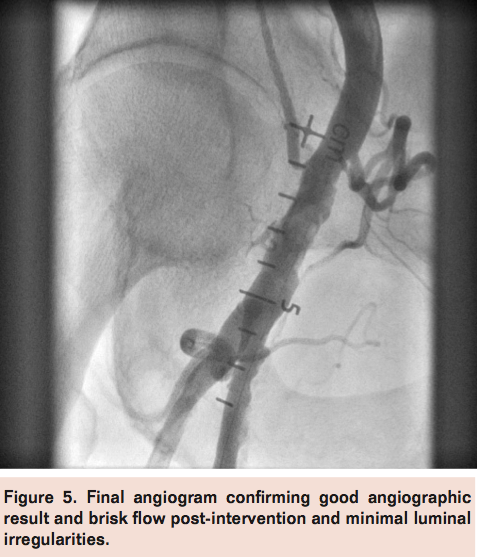

Access was obtained in the left femoral artery with a 7 Fr sheath. Angiography of the right external iliac artery with runoff demonstrated a hazy thrombotic 20 mm subtotal occlusion of the right common femoral artery at the site of previous Angio-Seal device deployment with filling of the distal common femoral artery via microchannels (Figure 2). A Grand Slam wire (Abbott Vascular) was advanced across the lesion into the distal popliteal artery and a Spider 6.0 mm distal embolic protection device (Covidien) was deployed in the popliteal artery. Directional atherectomy with a TurboHawk LSM device (Covidien) was performed (Figure 3) with multiple cuts to eliminate the residual Angio-Seal anchor and collecting some atheroma (Figure 4). The filter was retrieved successfully, which also revealed a moderate amount of macro debris (Figure 4). Final angiogram after adjunctive balloon angioplasty demonstrated good angiographic result with brisk flow through the common femoral artery and minimal residual luminal irregularities (Figure 5).